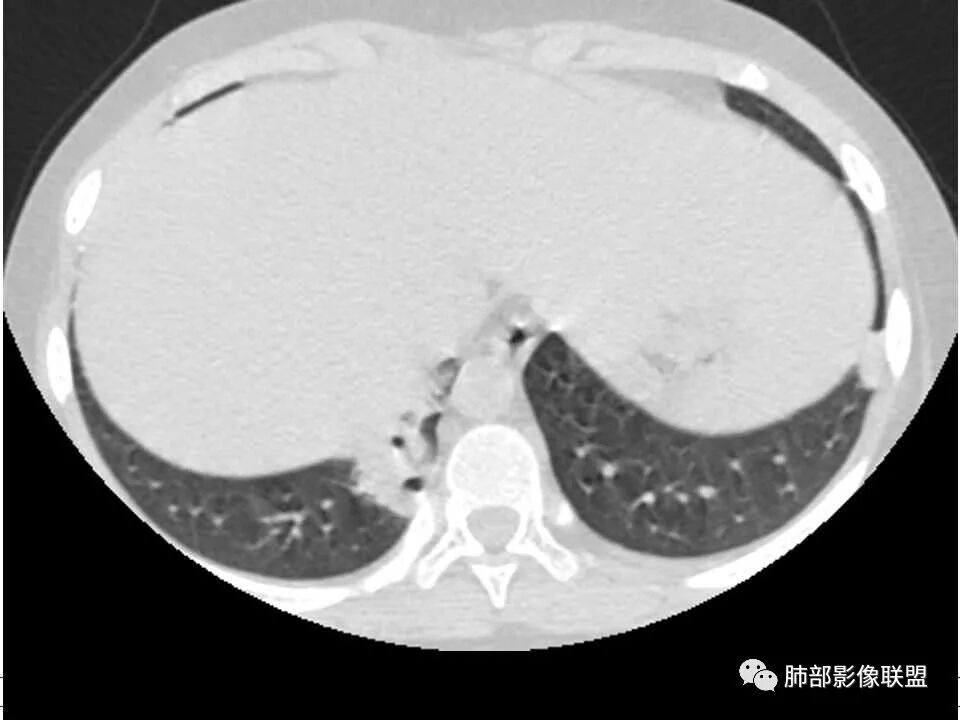

患者儿童,因右下肢疼痛伴肿胀14天就诊。病程中有发热及伴随症状。膝关节MRI提示右侧膝关节及右髌骨髁异常信号影,右膝髌上囊及关节腔内少量积液。胸部CT:双肺胸膜下多发结节影,部分结节空洞形成,且结节周围可见血管集束征。综合考虑血源性脓毒性肺栓塞、坏死性肺炎。右侧骨髓炎、血播性金葡菌肺炎,鉴别其他特殊感染及血管炎。

胸部ct:双肺多发空洞,结节,外带下叶为主,空洞内外光滑,有血管滋养征,综合病史及影像考虑脓毒性肺栓塞,结合病史,金葡可能性大。

2.双肺多发片影,随机分布,多空洞或囊腔,胸膜下多楔形影,气道未见受累等等符合脓毒血症影像学表现,尤其是金葡。

1. 多发胸膜下外周结节、< 3 cm 的楔形影和滋养血管征 CT 表现;

4.经恰当的抗生素治疗,肺部浸润影吸收。滋养血管征为一支血管影连接肺部周边病灶,在 2/3 以上患者出现,可作为高度提示 SPE 的征象。